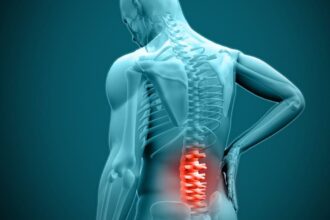

When Is Disc Surgery the Best Option for Your Condition?

Disc surgery, also known as spinal disc surgery, is a medical procedure aimed at addressing issues related to intervertebral discs…